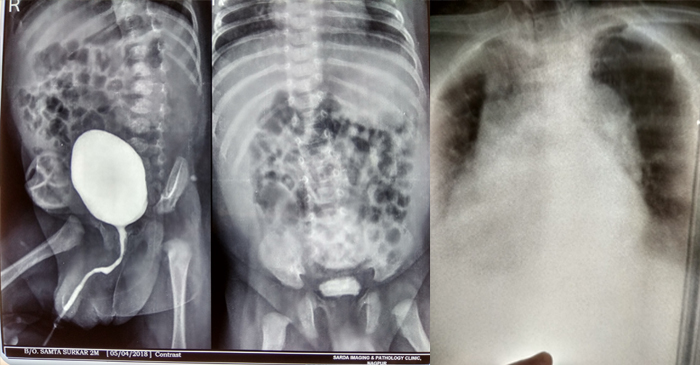

Radiology & Radio Diagnosis

- Sonography Unit : “Sonosite” M-Turbo

- Allenger X – Ray Unit

- Vision 100 X – Ray Unit

- 24*7 Radiologist